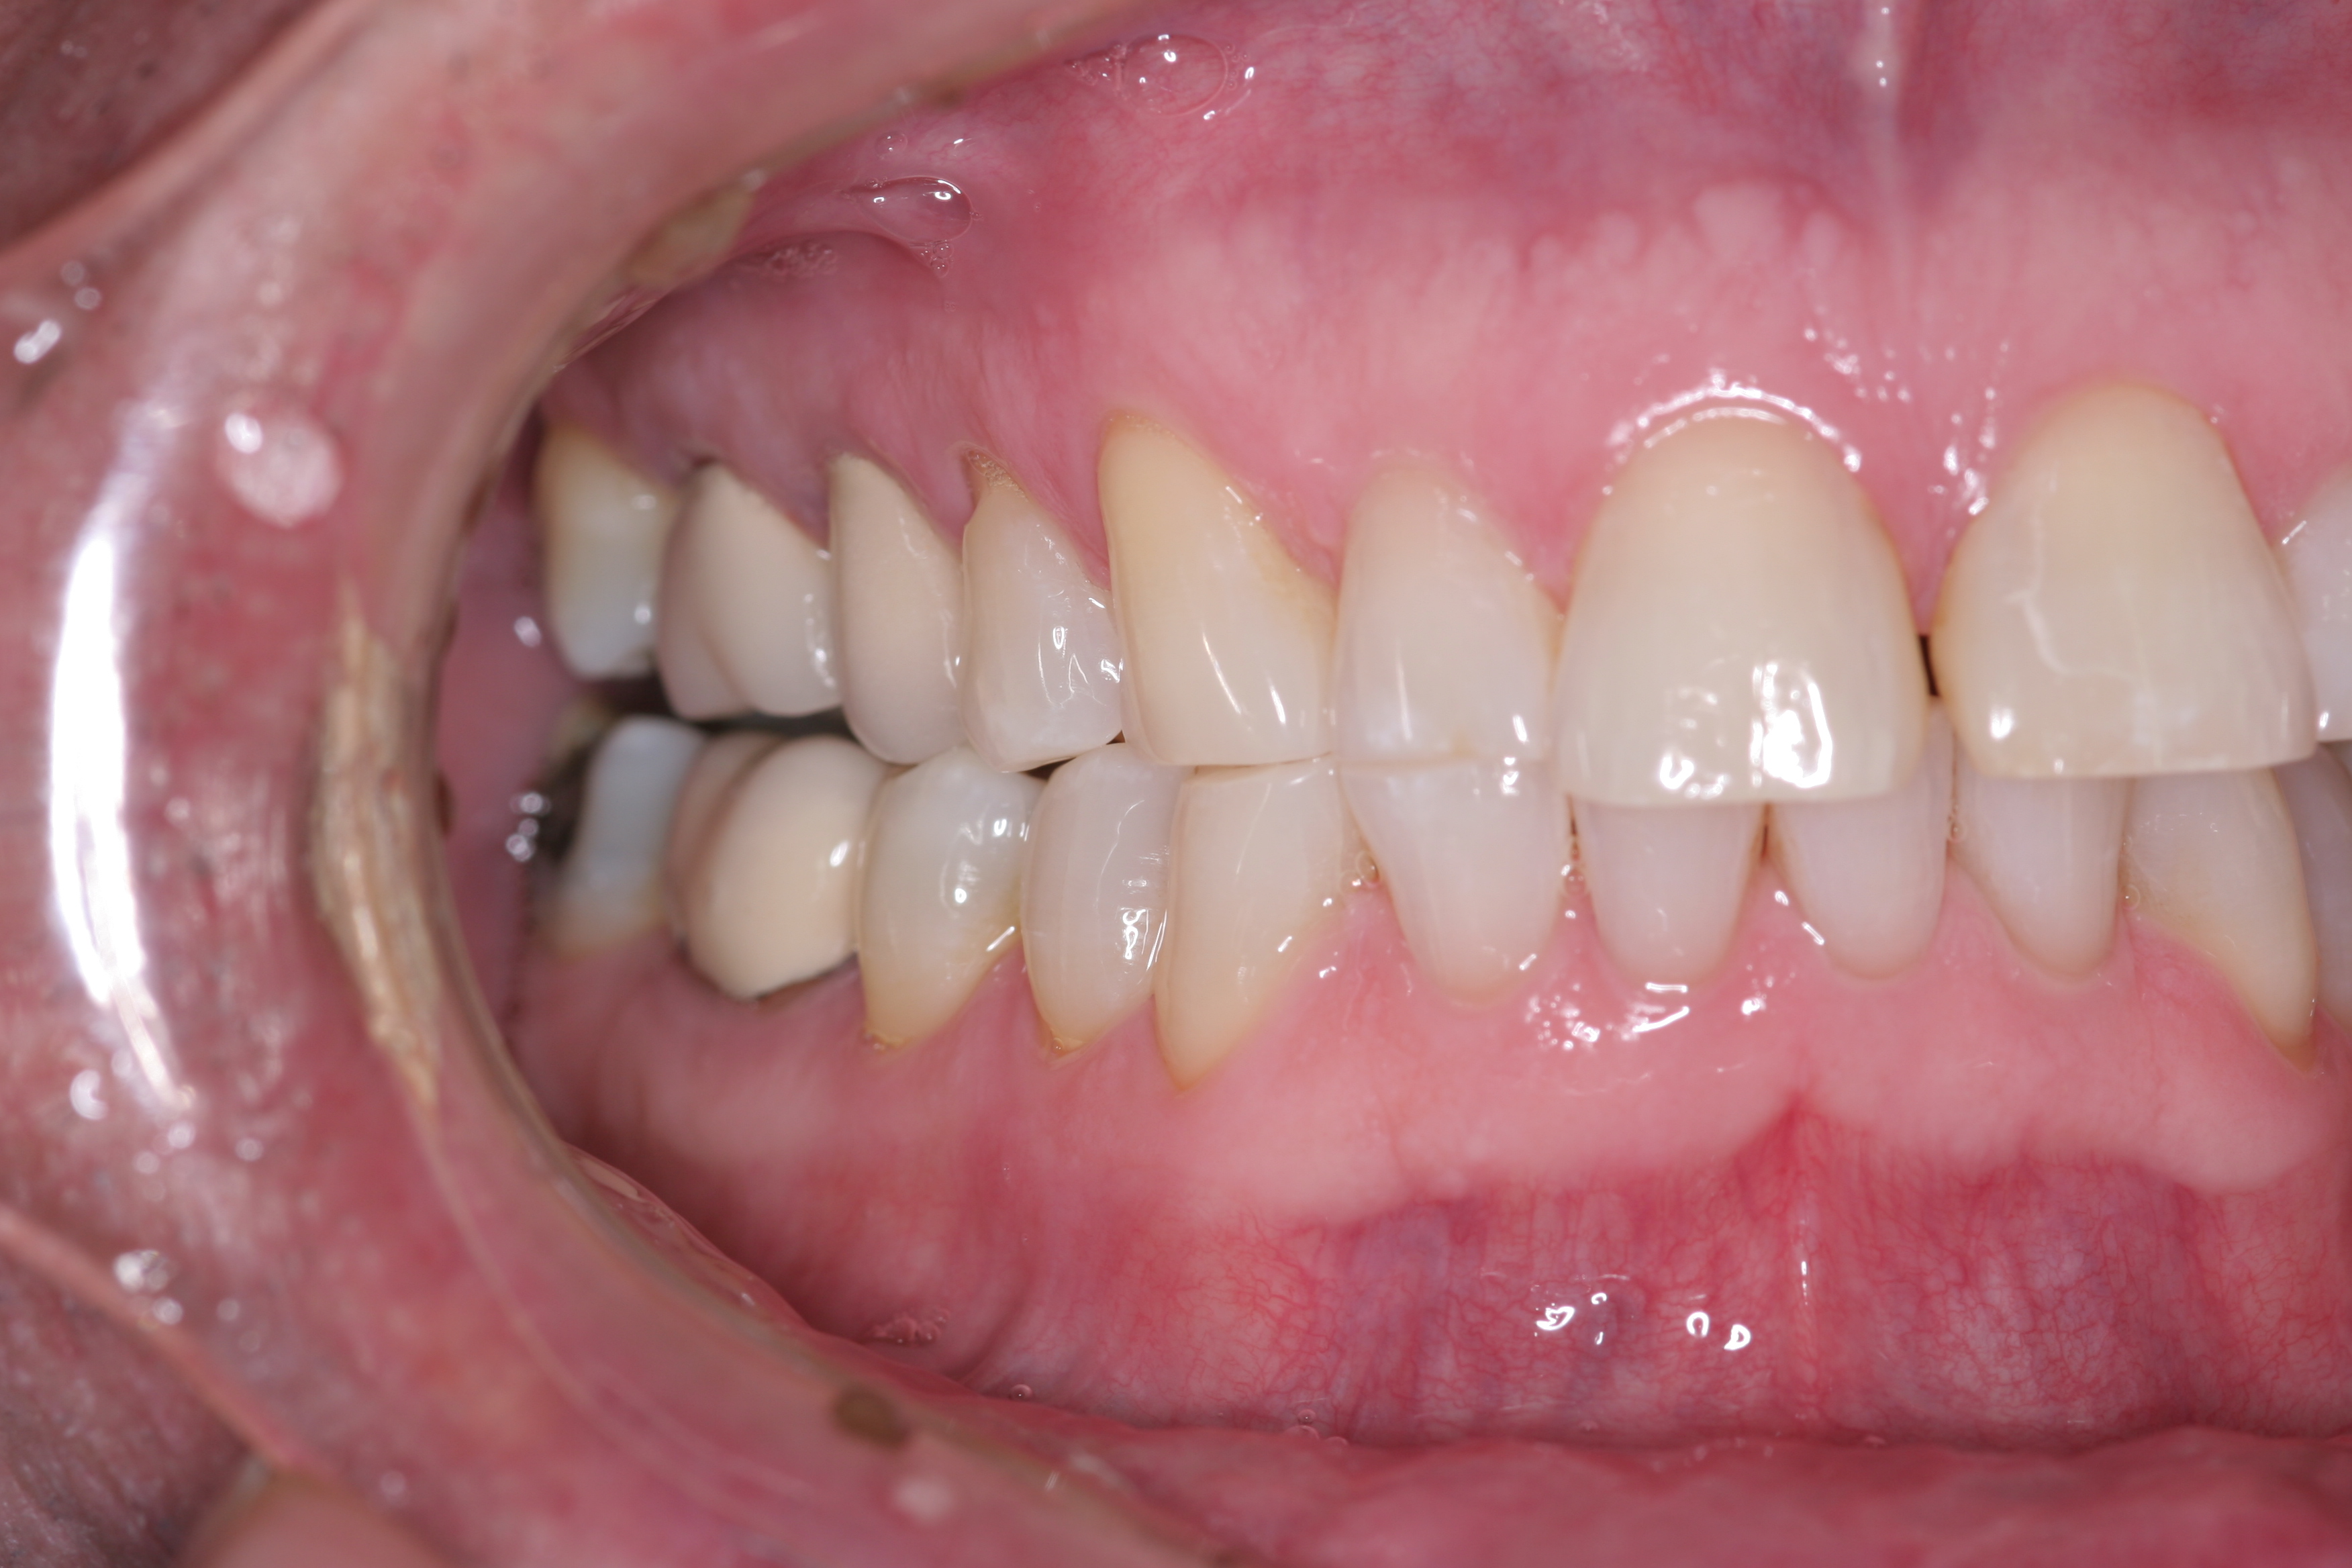

(3.) Either form of parafunction, whether conscious or unconscious, involves excessive rubbing together of the dentition.

Figure 3

(4.) CR/MIP discrepancies are very common and are major factors leading to excessive tooth-to-tooth abrasion.

Figure 4

True parafunctional bruxism is often rooted in central nervous system–mediated factors and can be influenced by psychosocial and peripheral factors.6 Parafunction may be conscious or unconscious. Either form involves excessive rubbing together of the dentition (Figure 3). CR/MIP discrepancies are very common and are major factors leading to excessive tooth-to-tooth abrasion (Figure 4). CR is the stable axial position the condyle reaches in the most superior and medial aspect of the glenoid fossa. According to Dawson, CR is the only condylar position that allows an interference-free occlusion.1 When the muscles of mastication contract, the condyles will seat into this anatomical position as long as there are no tooth contact interferences preventing the seat. Ideally, when a person closes, the joint will stay seated in CR and all the teeth will come in contact at the same time. Harmony will exist between seated joints and tooth contact.1 If the condyle is seated and the mandible rotates to allow full intercuspation, and posterior tooth inclines contact first, then the mandible slides down and forward around the interferences so that full tooth intercuspation can occur. However, this causes the condyle to be pulled out of CR and braced down the articular eminence by the lateral pterygoid muscle.7 This lack of harmony causes excessive wear as the teeth try to dictate MIP and the muscles work to seat the joint fully into CR. Tooth structure will often lose this “war” between muscles and teeth, resulting in excessive wear or breakage. Symptoms can also be evident in the temporomandibular joints (TMJs) and muscles themselves. This is why a complete examination reviewing all components of the stomatognathic system is critical. Although this topic is beyond the scope of this article, a complete diagnosis cannot be stressed enough.